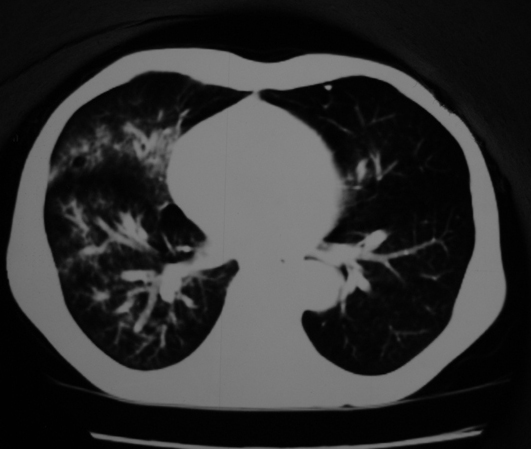

以下是引用同在2007-1-27 14:13:00的发言:[br]支持右侧中央型肺癌伴阻塞性病变.

以下是引用zjzjr在2007-1-27 16:56:00的发言:[br]支持右肺中心型肺癌伴阻塞性肺炎.